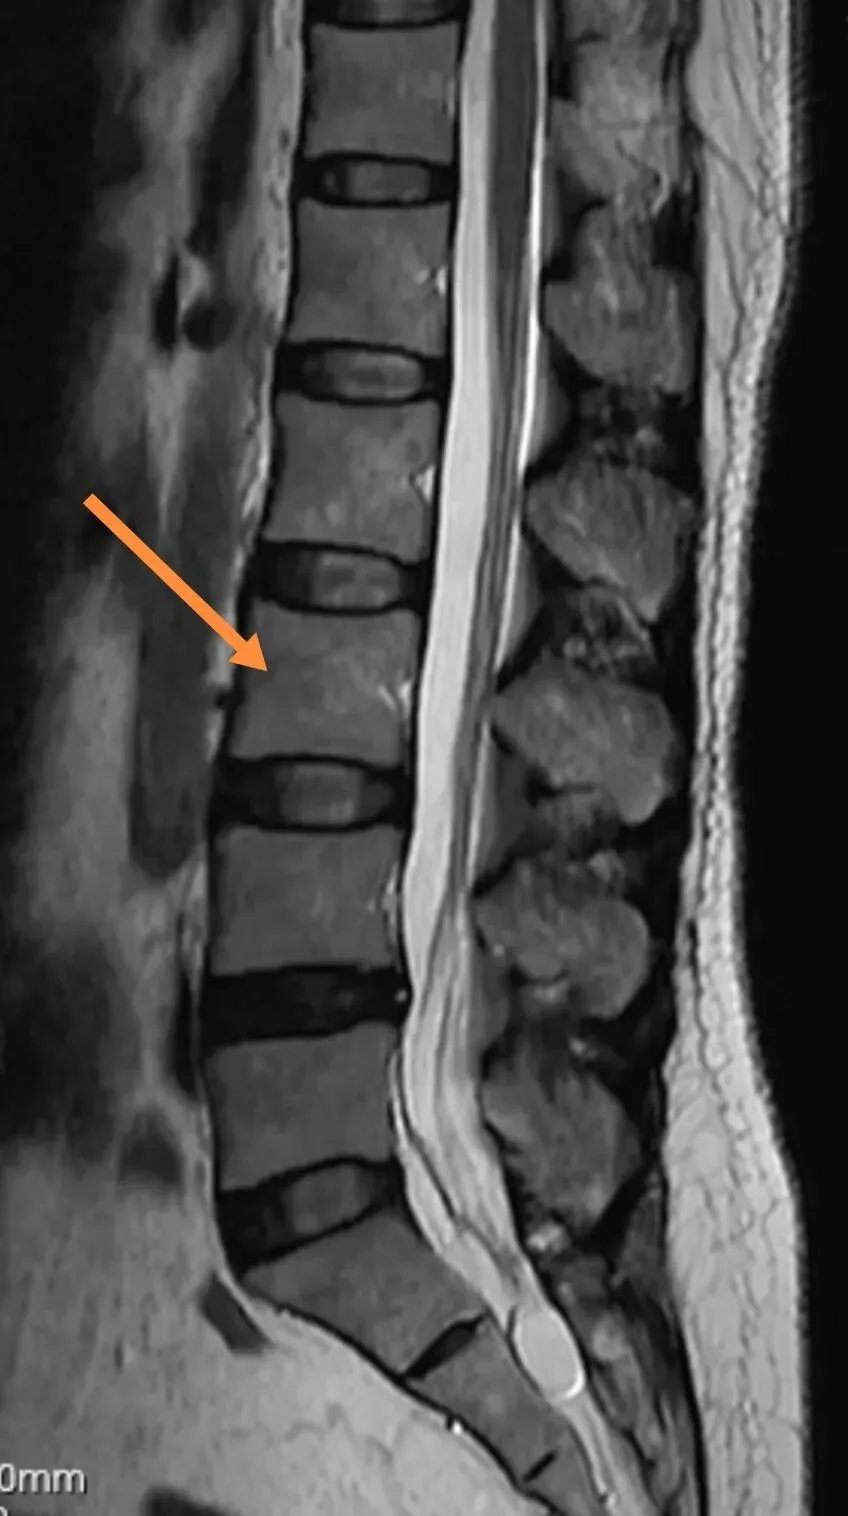

59、腰椎看图:L3

71、腰椎间盘突出CT直接征象:软组织影

73、X线摄影顺序

147、腰间盘突出病例

149、静脉窦成像的 MRV 图像